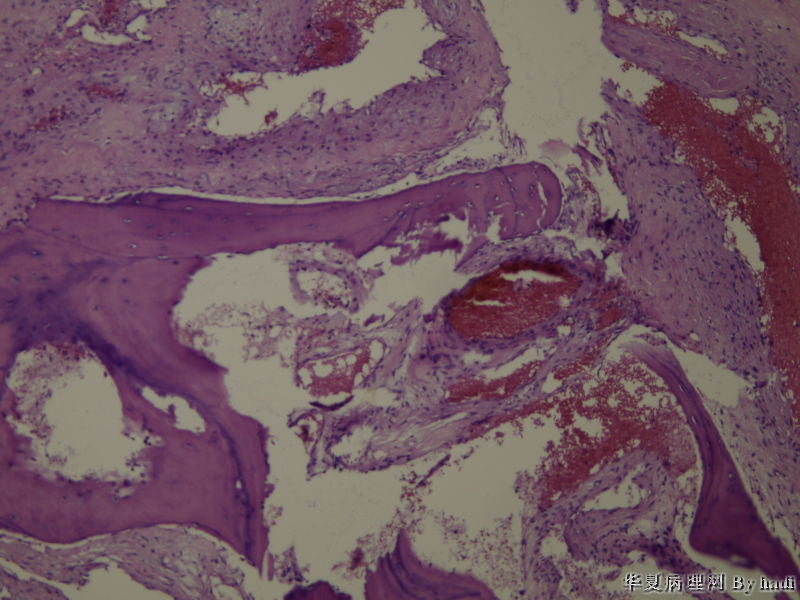

鼻腔肿瘤,成人男性

图1

纤维血管瘤?看不清间质有无异型